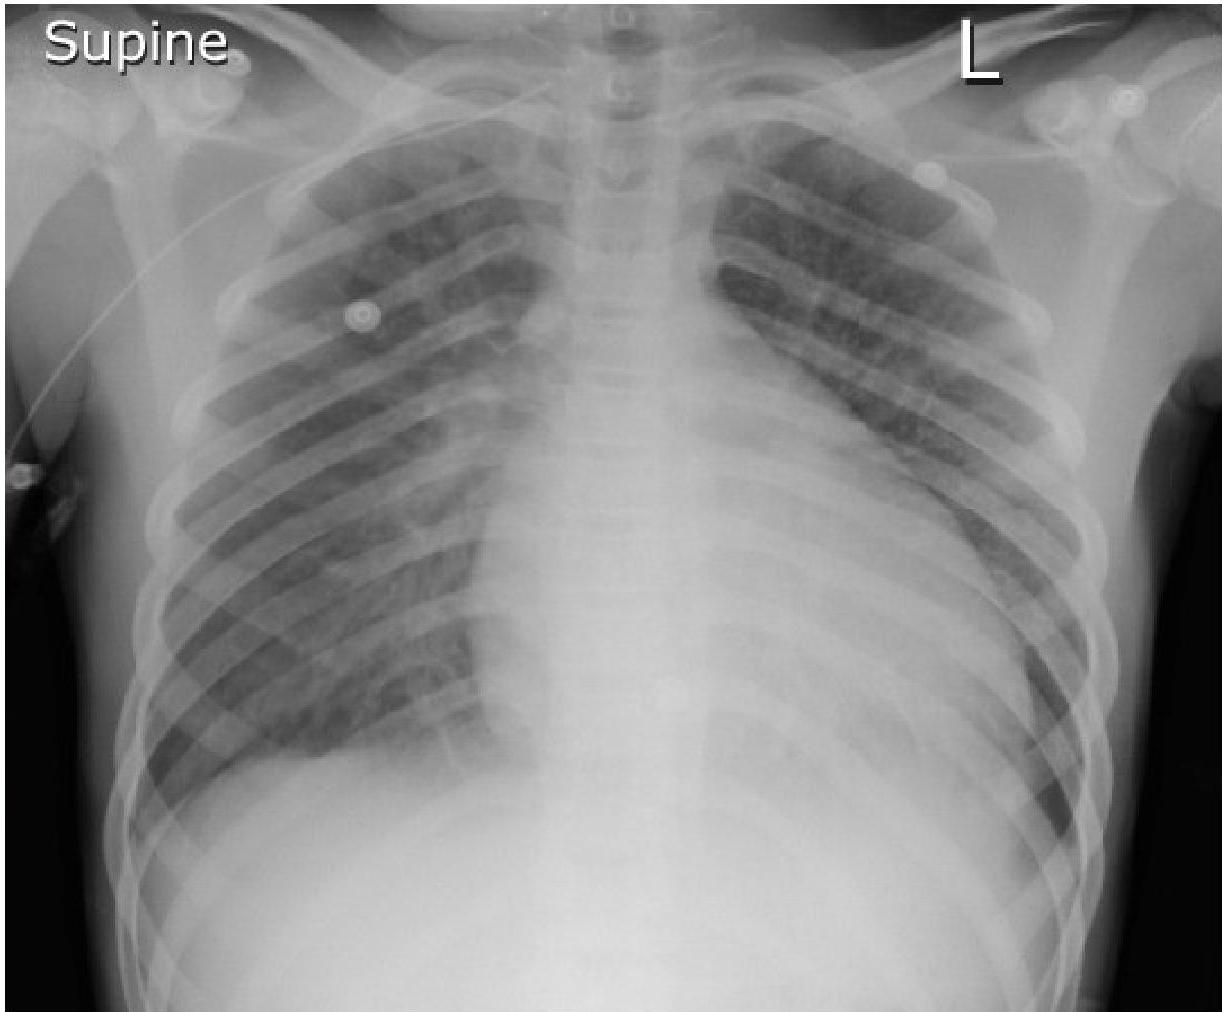

Chest Radiography

- Cardiomegaly: Left-to-right shunting defects, Dilated cardiomyopathy, Myocarditis, and Pericardial effusion.

- Pulmonary congestion/pulmonary edema.

- Pleural effusion.

- Pericardial effusion.

Chest radiograph of a 13-year-old boy with dilated cardiomyopathy